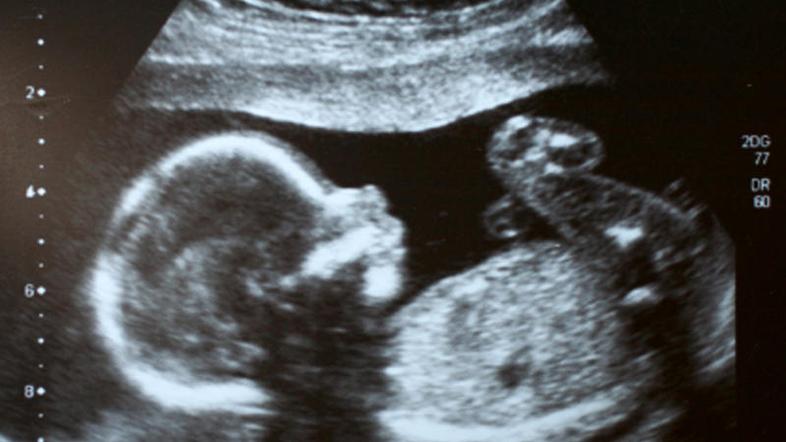

(Foto: istockphoto) Žurnal24 main

Starša Tadeja in Ivo K. sta obupana, saj njuni mrtvorojeni hčerki grozi, da jo bodo zavrgli kot medicinski biološki odpadek. Rodila se je namreč šest tednov prezgodaj, da bi ji pripadala pravica do potrdila o smrti in do pogreba.

"Mrtev otrok se je rodil star 16 tednov, kar je premalo, da bi ga šteli za otroka. Navadno patologi opravijo preiskave, nato pa se zarodek zavrže kot medicinski biološki odpadek. Ptujska bolnišnica se je včeraj z dopisom obrnila na ministrstvo za zdravje po pravno mnenje.  Da bi bila mogoča izročitev in pogreb, bi morali izdati potrdilo o smrti, kar pa ni mogoče, saj bi moral biti zarodek star vsaj 22 tednov. Odločitev je zdaj v rokah ministrstva za zdravje,“ pravi Pilinger.

Če nosečnost traja vsaj 22 tednov, mrtev plod velja za mrtvorojenega otroka, sicer pa gre za splav oziroma fetalno smrt, so nas na ministrstvu za zdravje opozorili na 17. člen Pravilnika o pogojih in načinu opravljanja mrliško pregledne službe.

"Plod rojen po 22. tednu nosečnosti se šteje za mrtvorojenega in skladno z Zakonom o matičnem registru je rojstvo mrtvorojenega potrebno prijaviti. Pred 22. tednom nosečnosti se rojen plod ne šteje za mrtvorojenega otroka, zato se v tem primeru ne more prijaviti rojstva in nadalje ravnati skladno z zakonom, ki ureja pokopališko in pogrebno dejavnost," so v odgovoru namignili, da kakršnakoli izjema ni mogoča.